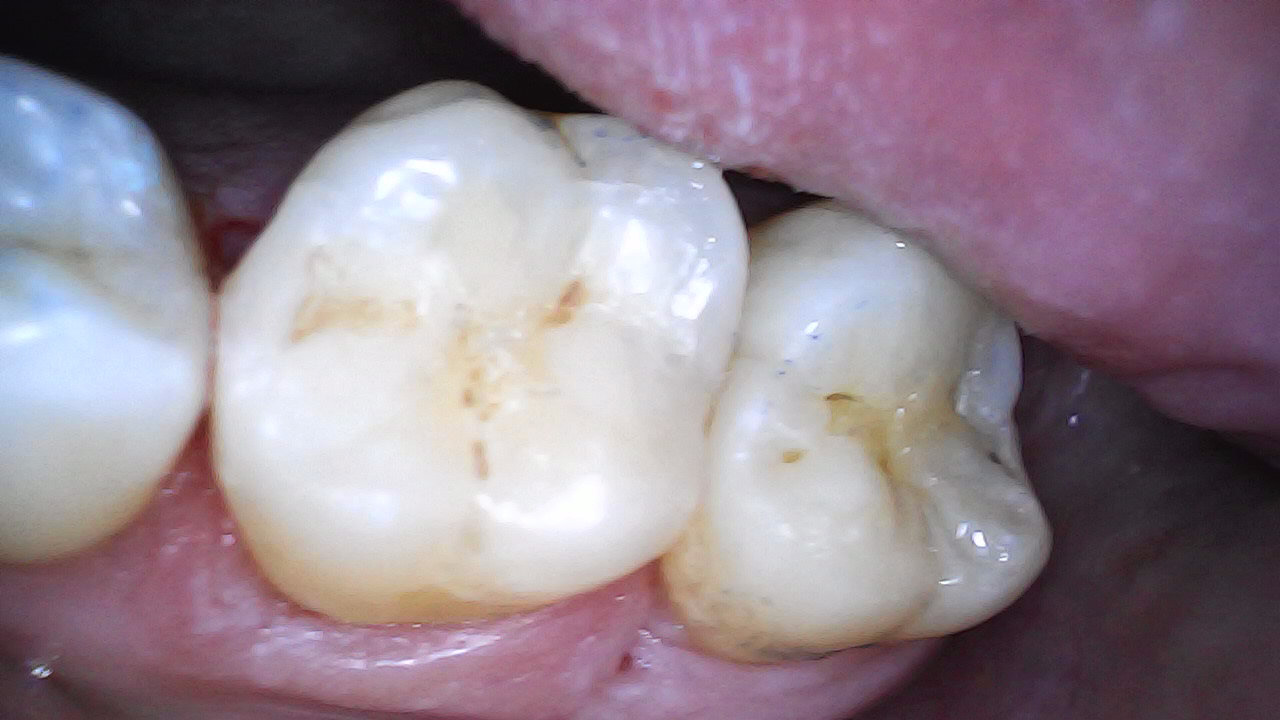

Initial

Composite restoration 37 and 36